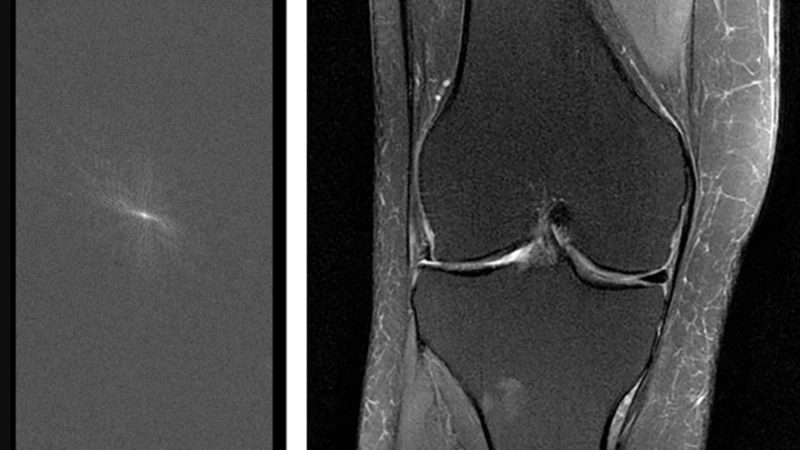

AIをこのように使うことのメリットは、人体の内部を医師に見せる画像を作成する際に、従来の手法(逆フーリエ変換と呼ばれる)よりもはるかに少ない情報量で済むことだ。「MRIでは、一定量のデータを集めて再構成法を使って画像を作成します」とニューヨーク大学ランゴーン・ヘルスの放射線科長マイケル・レヒト氏は言う。「しかし、これまでおそらく必要以上のデータを集めてきたことが判明しました」。燃費の良い車がガソリンを大量に消費するガタガタ車に取って代わるようなものだと考えてみよう。新しいアルゴリズムでは、MRI装置と同じ距離(この場合は正しい画像を取得する)を進むのに、より少ない測定から得られるデータしか必要としない。

放射線科医や外科医に必要な情報を提供し、この実験を成功と見なすためには、AI生成画像が2つの条件を満たしている必要があると、FAIRの研究科学者ラリー・ジトニック氏は説明する。まず、正確性が必要だ。靭帯の断裂を見逃したり、実際には存在しないものを偽造したりするような美しいスキャン画像は、役に立たないだけでなく、危険にもなり得る。次に、「放射線科医が画像を気に入る必要がある」とジトニック氏は言う。シアバラ医師のような医師が暗い読影室で何時間もスキャン画像を見つめるには、鮮明で目に優しい写真が必要だ。

しかし、このように実績のある機械が生成する情報をアルゴリズムに解釈させるのは容易なことではありません。AIソフトウェアが周波数データを正しく画像に変換できるように訓練するため、Facebookチームは実際のMRIスキャン情報を用いて約1,000種類の異なるモデルを試したと述べています。アルゴリズムに生の情報を与えるだけでなく、対応する画像も提示することで、ニューラルネットワーク(写真に写っているものを認識するなど、ソフトウェアエンジニアが様々なタスクを訓練できる一般的な機械学習ツール)が正しい画像を生成できるようにしました。

Facebookはモデルを開発した後、鋭い観察眼を持つ専門家によるブラインドテストを実施する必要がありました。シアバラ氏をはじめとするニューヨーク大学の放射線科医たちは、AIによって生成された膝のスキャン画像と従来の方法で作成された膝のスキャン画像を検証し、両方から同じ診断情報が得られるかどうかを検証しました。そして、どちらが正しいかを推測する必要がありました。患者を2回スキャンする(つまり、より遅い通常の方法と、より高速なAIを活用した方法)のではなく、チームは通常のスキャン画像から生データの一部を遡及的に抽出し、機械をより高速に動作させた場合の状況をシミュレートしました。

AIと放射線医学の融合というと、一般的にはアルゴリズムが画像を分析するものであり、Facebookとニューヨーク大学のプロジェクトのように画像を作成するものではありません。「これは非常に刺激的で重要な研究分野だと思います」と、デューク大学の准教授で放射線医学とAIを専門としているが、このMRI研究には関わっていないマチェイ・マズロウスキー氏は述べています。「これは、放射線医学におけるAI研究のほとんどとは異なるものです。」例えば、マズロウスキー氏はニューラルネットワークを用いて、超音波スキャンで甲状腺の結節を評価しました。他の研究では、機械学習を用いて胸部画像から結核などの問題を検出することに焦点を当てています。